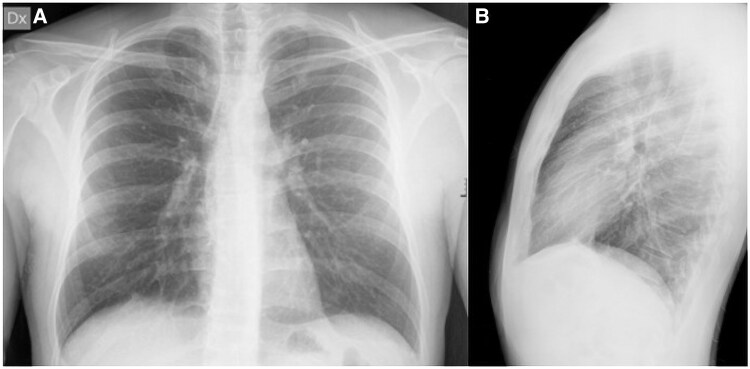

Case summary: We herein report the case of a 33-year-old male patient who presented to the Emergency Department with fever and chest pain after returning from a journey from a tropical region in Centre America. Initial tests showed elevated high-sensitivity troponin T (Hs-TnT) levels, suggesting possible cardiac involvement, but EKG and chest X-ray were normal. Echocardiography detected hypokinesis of the interventricular septum and a small pericardial effusion. Cardiac magnetic resonance (CMR) showed left ventricular function at lower normal limits and a small pericardial effusion, but also masses in the lungs and mediastinum, confirmed by computed tomography. Biopsy was performed, and histology revealed disseminated histoplasmosis. The patient was treated with antifungals and was discharged after two weeks, continuing antifungal administration in the outpatient clinic for 18 months. Follow-up imaging showed significant reduction of the masses. The patient remained asymptomatic with no further treatment needed.